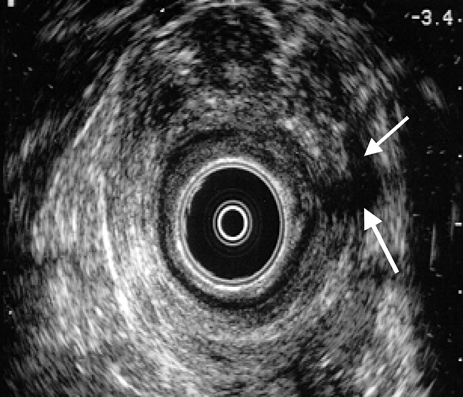

Imagen hipoecogénica a nivel izquierdo, compatible con fístula transesfinteriana en paciente con enfermedad de Crohn (flechas)